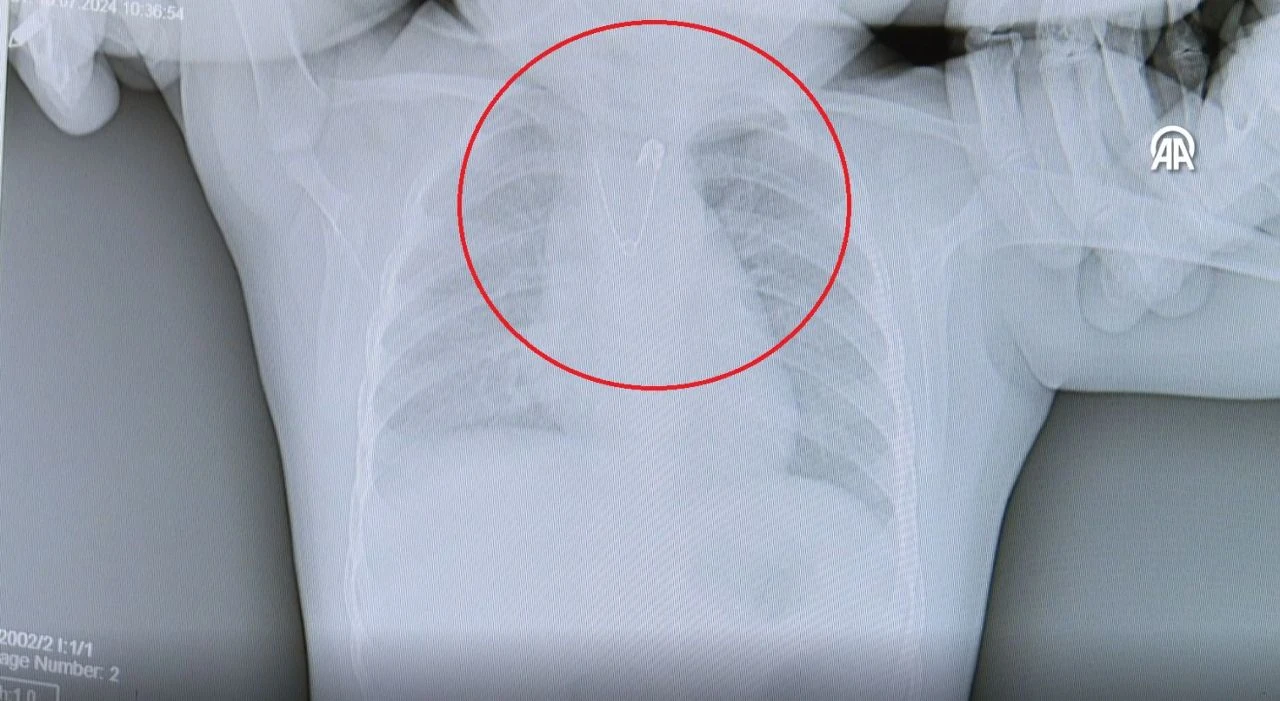

Annenin bu esnada bebeğinin yakasına takılan duanın çengelli iğnesinin olmadığını fark ettiğini ve ailenin bunun üzerine hemen acil servise başvurduğunu belirten Çalışkan, "Bebeğimizin acil serviste çekilen akciğer grafisinde açık ağızlı bir çengelli iğnenin yemek borusunun en dar yeri olan üst kısmı tıkadığını gördük.

Bu da çocuğumuzun kusmasına, beslenememesine neden oluyordu. Hemen ameliyathaneye alarak anestezi altında yapılan endoskopi işlemiyle çengelli iğneyi çıkarttık." bilgisini paylaştı.